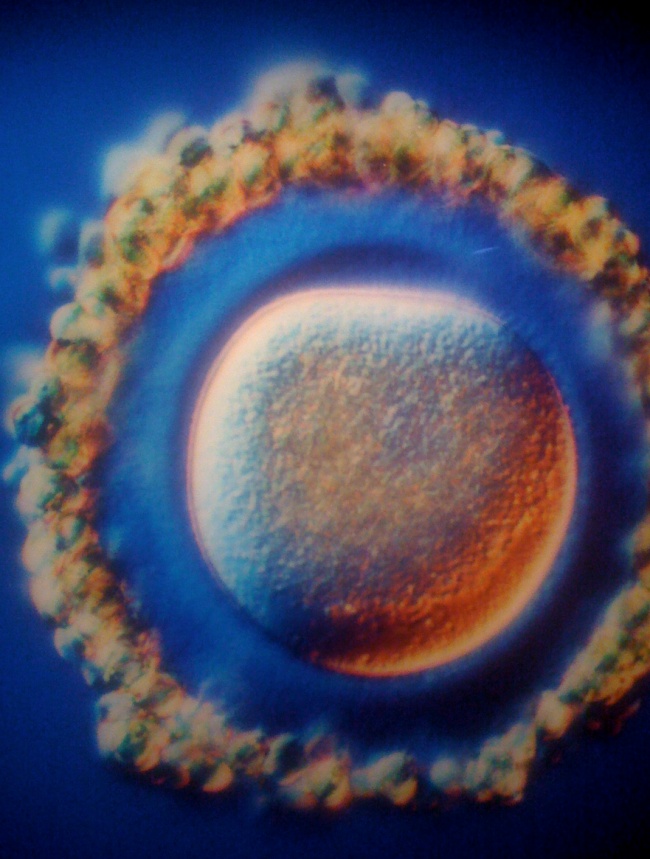

A petesejt.

A mindent eldöntő pillanat: amikor a hímivarsejt találkozik a petesejttel.

Az apa (körülbelül) 40-360 millió ivarsejtjéből egy áttöri a petesejt hártyáját.

Az ivarsejt fejében található az összes örökítőanyag.